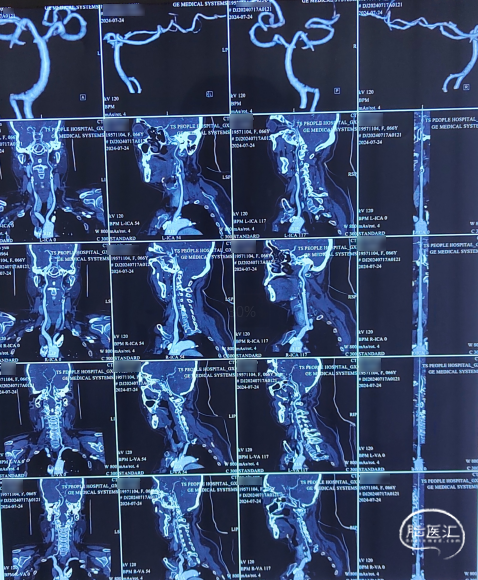

头颈部CTA影像及报告(2024-07-24)。

入院头颈部CTA影像及报告(2024-09-05)。